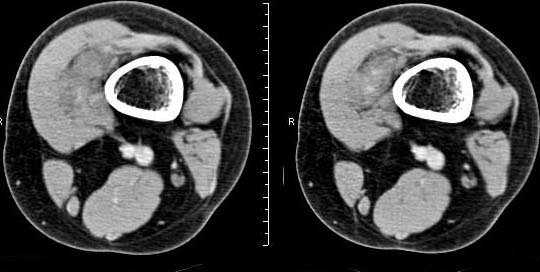

女,24岁,左大腿下部近膝关节处偏内侧有一软组织包块,触之有压痛,平扫示病灶密度不均,形态及轮廓欠规则,无包膜,与周围组织界限不清,增强后显示有明显强化且不均匀强化,本人考虑为该软组织肿块为恶性病变。请大家发表高见!

病灶是有不均匀强化,但病灶与周围组织分界较清,所以性质难定。支持!建议穿刺活检!

病理结果:血管瘤。

非常遗憾,我们的ct板块就是ct的内容,没有把mri图像有机地结合起来,其实很多骨与关节病变,特别是肢体软组织的病变mri还是相当有意义的。